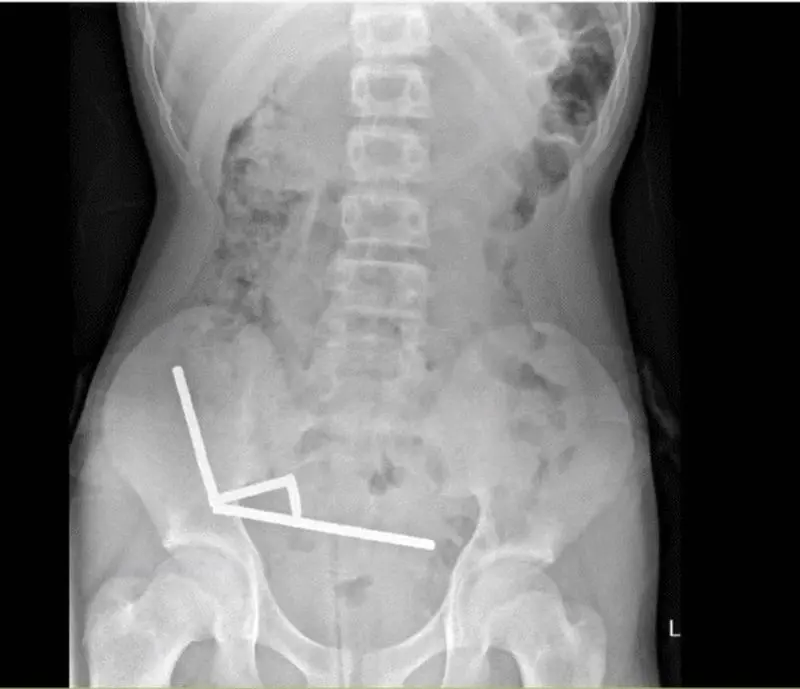

| فرارو-یک نوجوان 13 ساله در نیوزیلند پس از بلعیدن نزدیک به 200 آهنربای قوی به دلیل آسیب دیدگی روده تحت عمل جراحی قرار گرفت. به نقل از sciencealert،به گفته پزشکان بیمارستان تائورانگا ، این نوجوان حدود یک هفته پیش از مراجعه به بیمارستان، ده ها آهنربای نئودیمیومی بلعیده بود. او ابتدا تصور می کرد حدود 100 عدد آهنربا بلعیده است، اما تصویربرداری نشان داد که بیش از 190 آهنربا در بخش های مختلف روده او تجمع کرده اند. تصاویر رادیولوژی، چهار زنجیره بلند از آهنرباها را در بخش های جداگانه روده نشان داد. این ذرات فلزی کوچک درون بدن به هم متصل شده و باعث انسداد، پارگی و مرگ بخشی از بافت روده بر اثر فشار مغناطیسی شدند. در نهایت، پزشکان ناچار شدند بخشی از روده را خارج کنند.به گفته تیم درمان، وضعیت عمومی این نوجوان پس از عمل جراحی رضایت بخش است و او پس از هشت روز بستری، از بیمارستان مرخص شد.  زنجیره های آهنربایی در شکم نوجوان نیوزیلندی الکس سیمز، پژوهشگر دانشگاه اوکلند، در واکنش به این حادثه گفت: بلعیدن آهنرباهای کوچک و قوی می تواند تهدیدی جدی برای جان کودکان باشد. متأسفانه این آهنرباهای کوچک معمولاً در قالب توپ های رنگارنگ و براق و به عنوان اسباب بازی یا ابزار ضد استرس عرضه می شوند و ظاهر فریبنده آن ها توجه کودکان را به خود جلب می کند. به گفته مسئولان نیوزیلندی، یکی از چالش های پرخطر در شبکه های اجتماعی، استفاده از آهنربا برای ساخت پیرسینگ مصنوعی روی زبان یا لب است؛ اقدامی که تاکنون موارد متعددی از بلع تصادفی و جراحی های اضطراری را رقم زده است.  زنجیره های آهنربا که در شکم نوجوان نیوزیلندی یافت شدند. با وجود اینکه نیوزیلند از سال 2013 فروش آهنرباهای نئودیمیومی را به طور کامل ممنوع کرده، اما گزارش ها نشان می دهد که بسیاری از خانواده ها همچنان از فروشگاه های اینترنتی خارجی، این محصولات را خریداری می کنند. پزشکان می گویند اجرای ممنوعیت ها در فضای آنلاین دشوار است و والدین باید بر خریدهای اینترنتی کودکانشان نظارت داشته باشند. در گزارش بیمارستان تائورانگا آمده است: دسترسی کودکان به آهنرباهای قوی، نگرانی رو به رشدی در حوزه سلامت اطفال محسوب می شود. در صورت بلع حتی یک آهنربا، مراجعه فوری به بیمارستان ضروری است؛ چرا که بیش از 75 درصد از بیماران به جراحی یا آندوسکوپی نیاز پیدا می کنند.ـ |